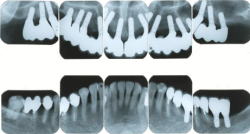

| 症例1 重症の歯周炎に対するインプラント治療(歯を数本失った場合) | ||||||||||||||||||||||||||||||||||

|

| ||||||||||||||||||||||||||||||||||

| 症例2 重度の歯周炎に対するインプラント治療(上の歯をすべて失った場合) | ||||||||||||||||||||||||||||||||||

| 症例3 重症の歯周炎・虫歯と不正咬合に対するインプラント治療 | ||||||||||||||||||||||||||||||||||